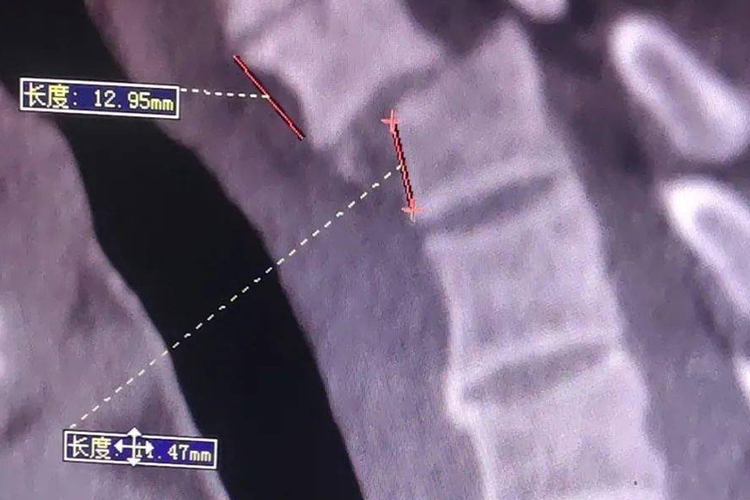

多见于颈椎滑脱,表现为颈部疼痛难忍,并伴随手臂和手指等部位出现无力、发麻等不适,甚至不能站立的症状,检查可见颈椎第七节滑脱。

颈椎第七节突出若是生理现象,与正常的机体发育有关;若是颈椎滑脱,多与外力撞击、椎间盘退变等原因有关,导致正常的椎体位置错位。

颈椎第七节突出若是生理现象则无需处理,若是颈椎滑脱,则建议遵医嘱使用手术切开复位内固定治疗,同时可遵医嘱使用布洛芬缓释胶囊等药物缓解疼痛症状。